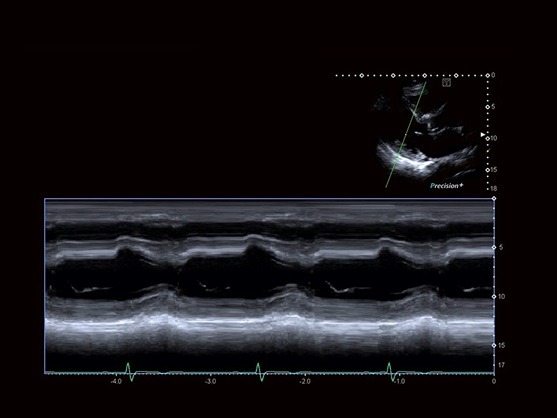

Flex-M به شما اجازه می‌دهد که رد های آناتومیک درستی را در تصویر M mode از روی تصاویر زنده یا ذخیره شده با کیفیت یکسان به دست آورید